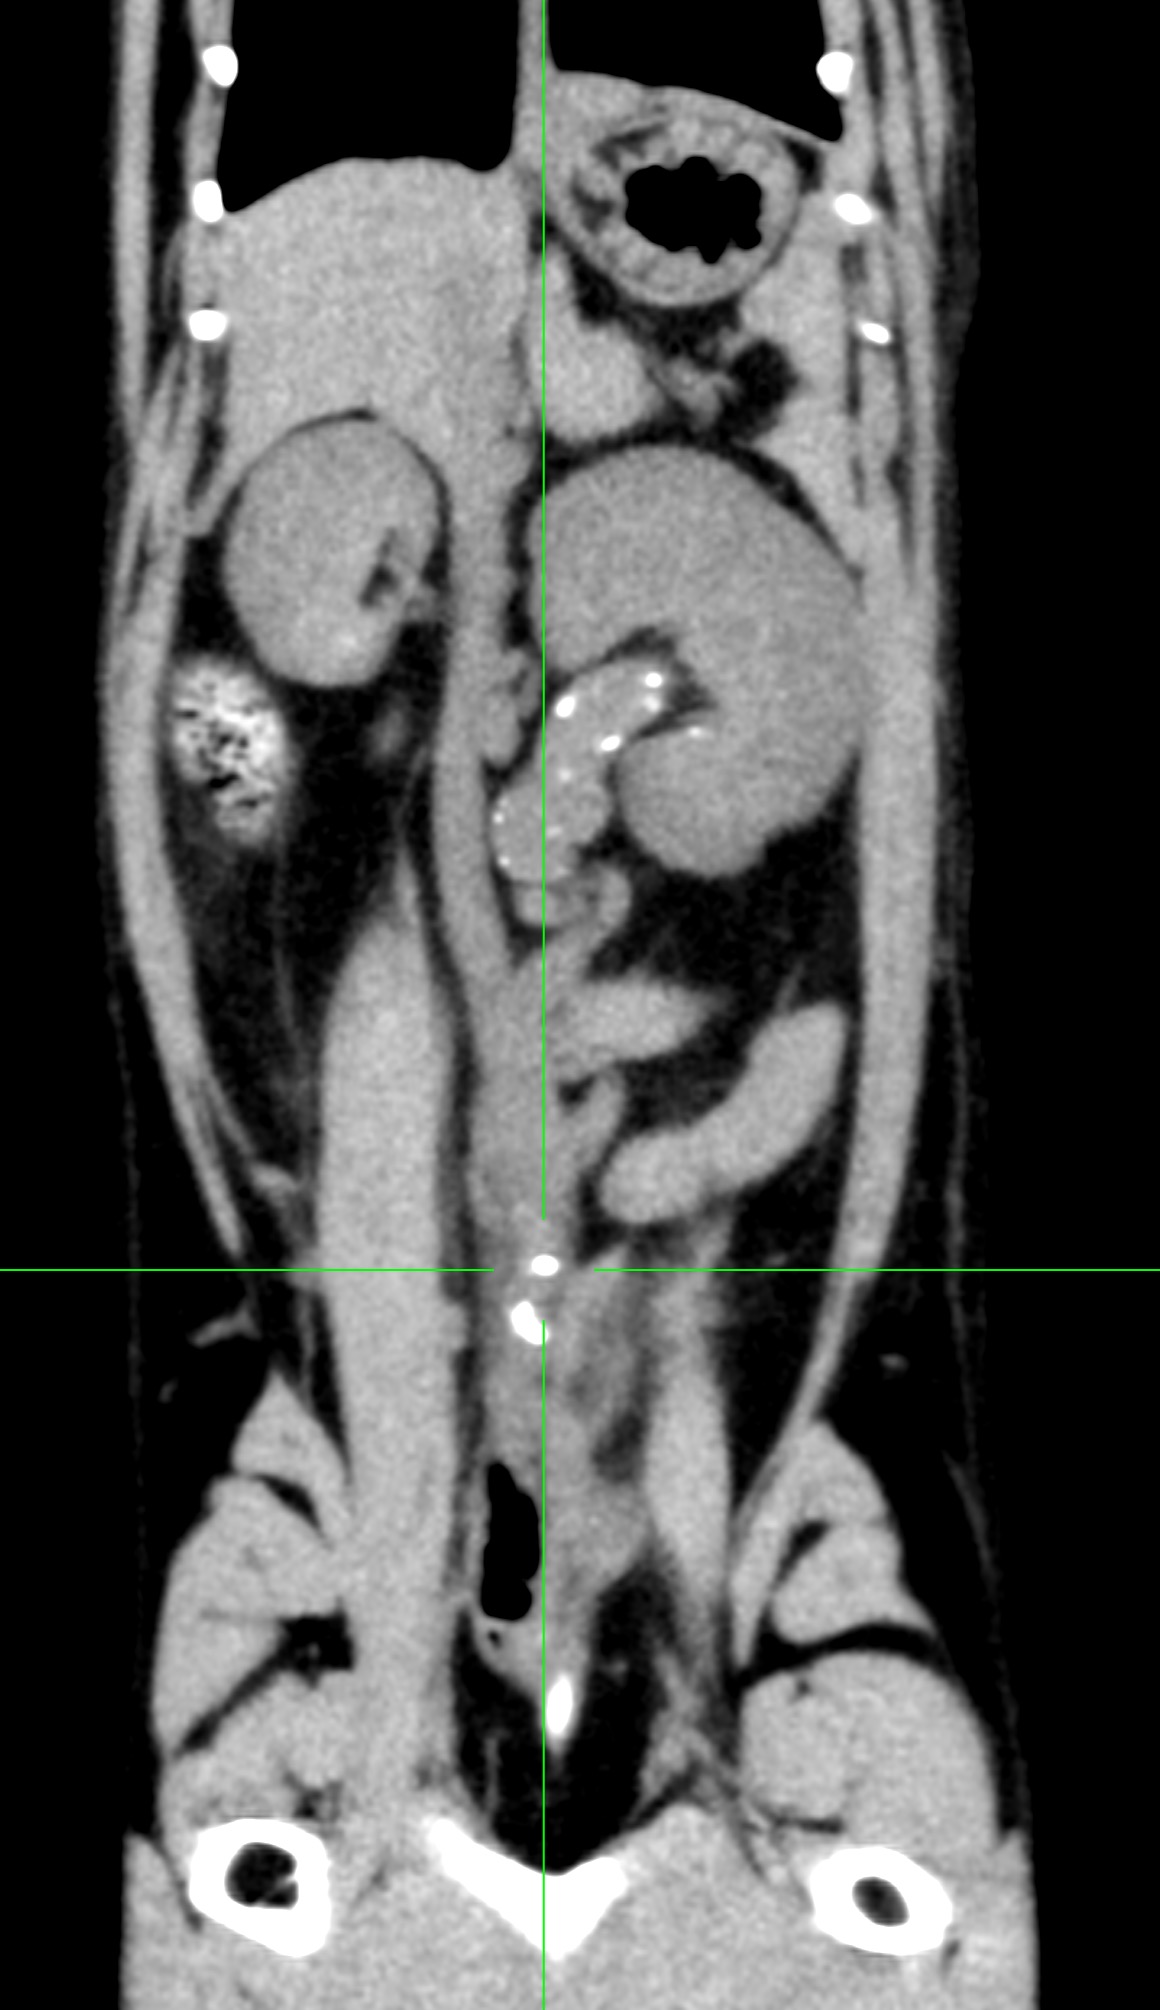

猫さんが尿管結石で腎臓の数値が上昇しているので何とかして欲しい。かかりつけの先生から連絡がありました。血液検査では腎数値が中程度に上昇しています。CTでは尿管内、腎盂内に複数の結石が認められており、尿管結石が閉塞→尿管炎→線維化→内腔の狭窄を呈しています。顕微鏡下マイクロサージェリーで狭窄した領域の尿管を切除し、膀胱と新吻合術を行いました。